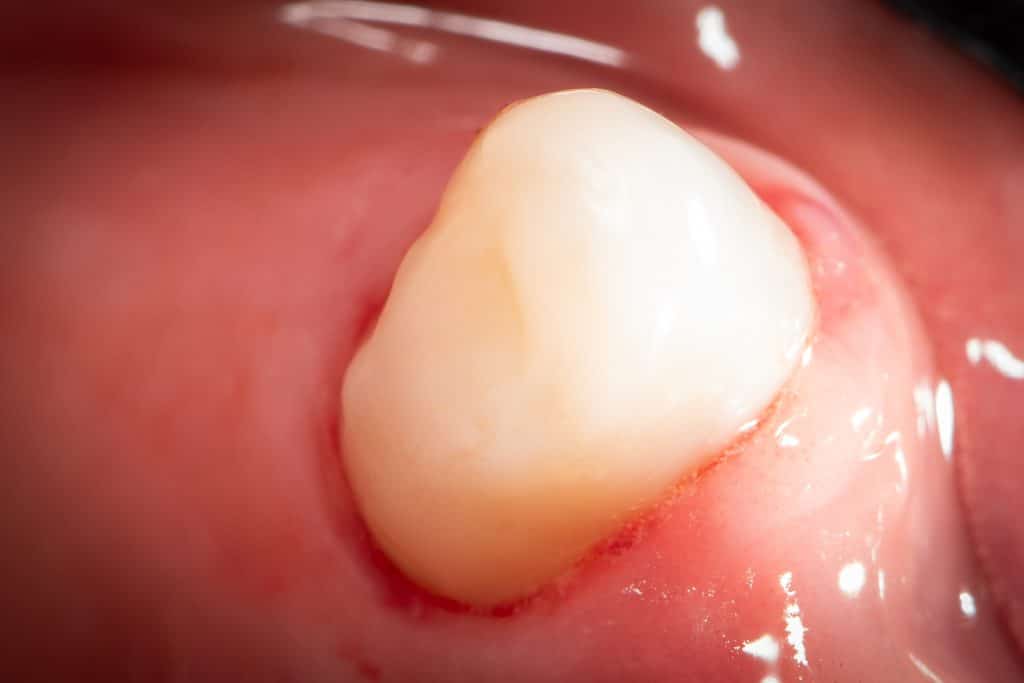

Tooth no23 with more than 14 years old filling.this type of treatment was good at its time and circumstances .Today, it is preferable to choose a treatment that reduces the risk of catastrophic failure and preserves the tooth structure for future interventions if anything goes wrong , as this will prolong the TOOTH’s longevity.